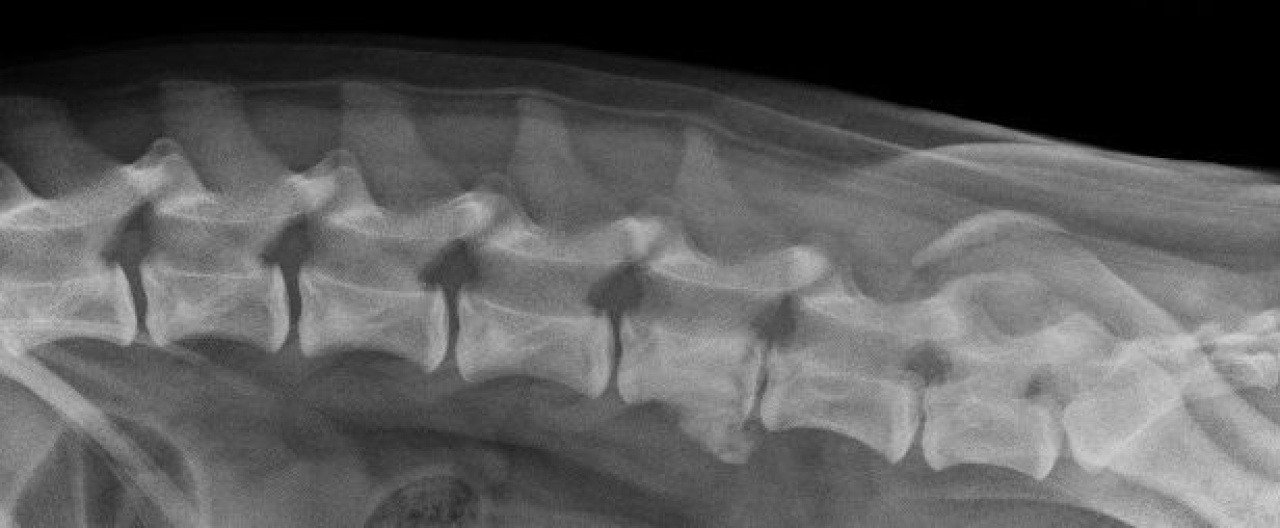

From www.researchgate.net

Lateral radiographs of the lumbar spine of a dog weighing 15 kg Lumbar Spine In Dogs By marc kent, dvm, dacvim (neurology) article. Abnormal development of the vertebrae in the neck squeezes the spinal cord in dogs with cervical spondylomyelopathy (also called. Canine degenerative lumbosacral stenosis (dlss) describes a syndrome in dogs associated with degeneration of the structures. Degenerative lumbosacral stenosis in dogs. Degenerative lumbosacral stenosis (dlss) is the most common cause of compression of the. Lumbar Spine In Dogs.